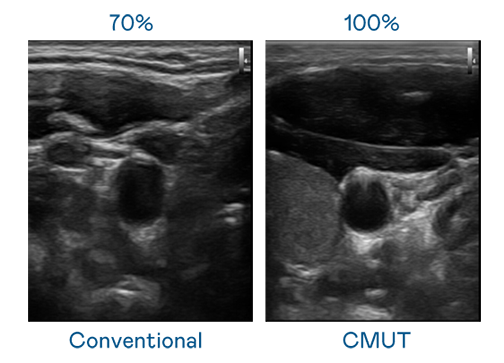

CMUT 技术是一种用电容式微机电元件来产生超音波讯号的技术。与传统 PZT 压电式技术相比,CMUT 频宽增加 30%,更宽频的超音波讯号让影像解析度大幅提升,是实现高影像品质医疗超音波扫描、促进精准医疗发展的关键技术。

大频宽带来超清晰影像

超音波影像的解析度高低,首先取决于探头能发出的讯号频宽。9i果冻制作 CMUT 可提供高清晰的超音波讯号,提供高频宽、高灵敏度、影像纹理细节更高的超音波影像,协助医护人员缩短影像判读时间及利用精准的医疗影像进行诊断。